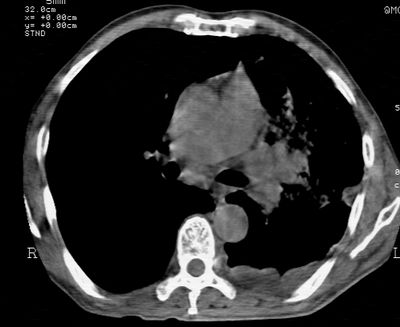

标题: CT24000:M65,胸痛,胸闷月余,既往慢支,肺气肿,肺心病 [打印本页]

标题: CT24000:M65,胸痛,胸闷月余,既往慢支,肺气肿,肺心病

左肺门肿块,相应支气管闭塞,左肺上叶、舌叶大片及散在高密度影,部分呈不张改变,两肺纹粗乱,左侧胸腔积液。考虑左侧中央型肺癌伴阻塞性改变。

左肺门见巨大软组织肿块影,直径约--,境界清,左上肺叶支气管变窄,左上肺舌叶见大片状密实影,余肺纹理增多、紊乱、纤细、部分网格状,两肺透亮度增高,纵隔内见增大多发淋巴结影,心影略左偏,左侧少量胸腔积液。

左侧中央型肺癌伴左上肺舌叶不张、纵隔淋巴结转移,左侧少量胸腔积液。